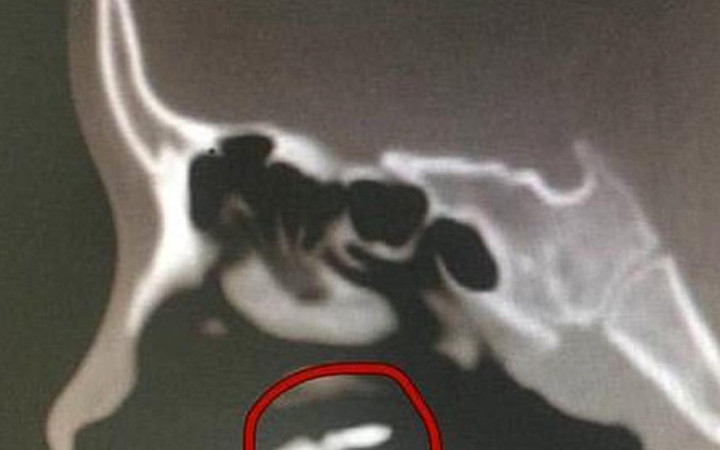

Röntgen çeken doktorlar Zhang’ın burun boşluğunda şüpheli bir pıhtıya rastladı. Daha sonra bunun bir diş olduğu anlaşıldı.

Hastanın 1999 yılında 10 yaşındayken bir alışveriş merkezinin üçüncü katından düştüğü ve iki dişini kaybettiği ortaya çıktı.

Kazanın ardından doktorlar sadece bir dişi bulurken, kayıp olan dişin buruna geçtiği ve vücut yabancı bir madde gibi algılamadığı için orada kök saldığı tespit edildi.